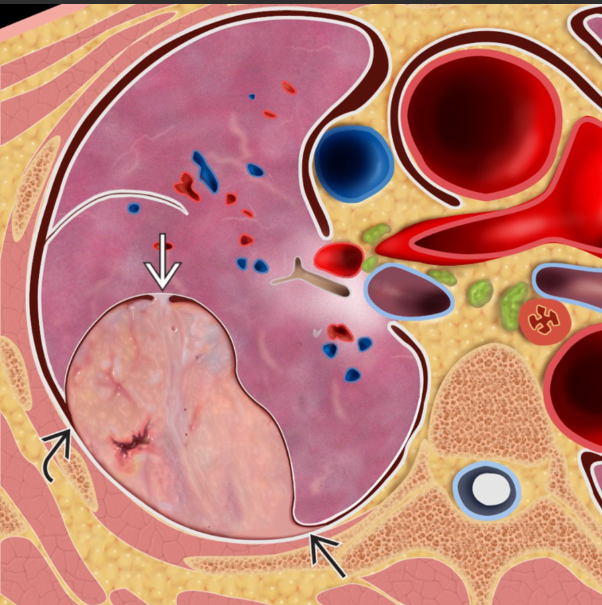

Aspectos macroscópicos do tumor fibroso. A massa está aderida à pleura visceral por um pedículo (seta sólida branca) e apresenta: Aspecto nodular em redemoinho (whorled) Focos de necrose ao corte Em relação à pleura adjacente: Ângulos obtusos com a pleura (seta sólida preta) são característicos Entretanto, lesões volumosas podem formar ângulos agudos com a pleura (seta curva preta) na imagem seccional (TC/RM)